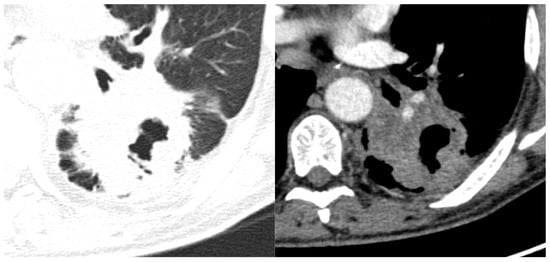

Considering the exclusion criteria previously mentioned, a total of 58 patients were analysed in this study, in which 26 cases were pathologically proven to be adenocarcinoma (Figure 1), 22 cases were shown to be squamous cell carcinoma (Figure 2), and 10 cases were shown to be small cell lung cancer (Figure 3).

Figure 3.

Axial CT of four different cases of small cell lung cancer: (A) right hilar mass with segmental atelectasis and expansion into the right main bronchus; (B) left voluminous mass with central necrosis, pleural invasion and periaortic extension; (C) small-sized central right tumour with paratracheal location; and (D) central left tumour with important mediastinal invasion involving the pulmonary trunk, left pulmonary artery, left main bronchus, and oesophagus.